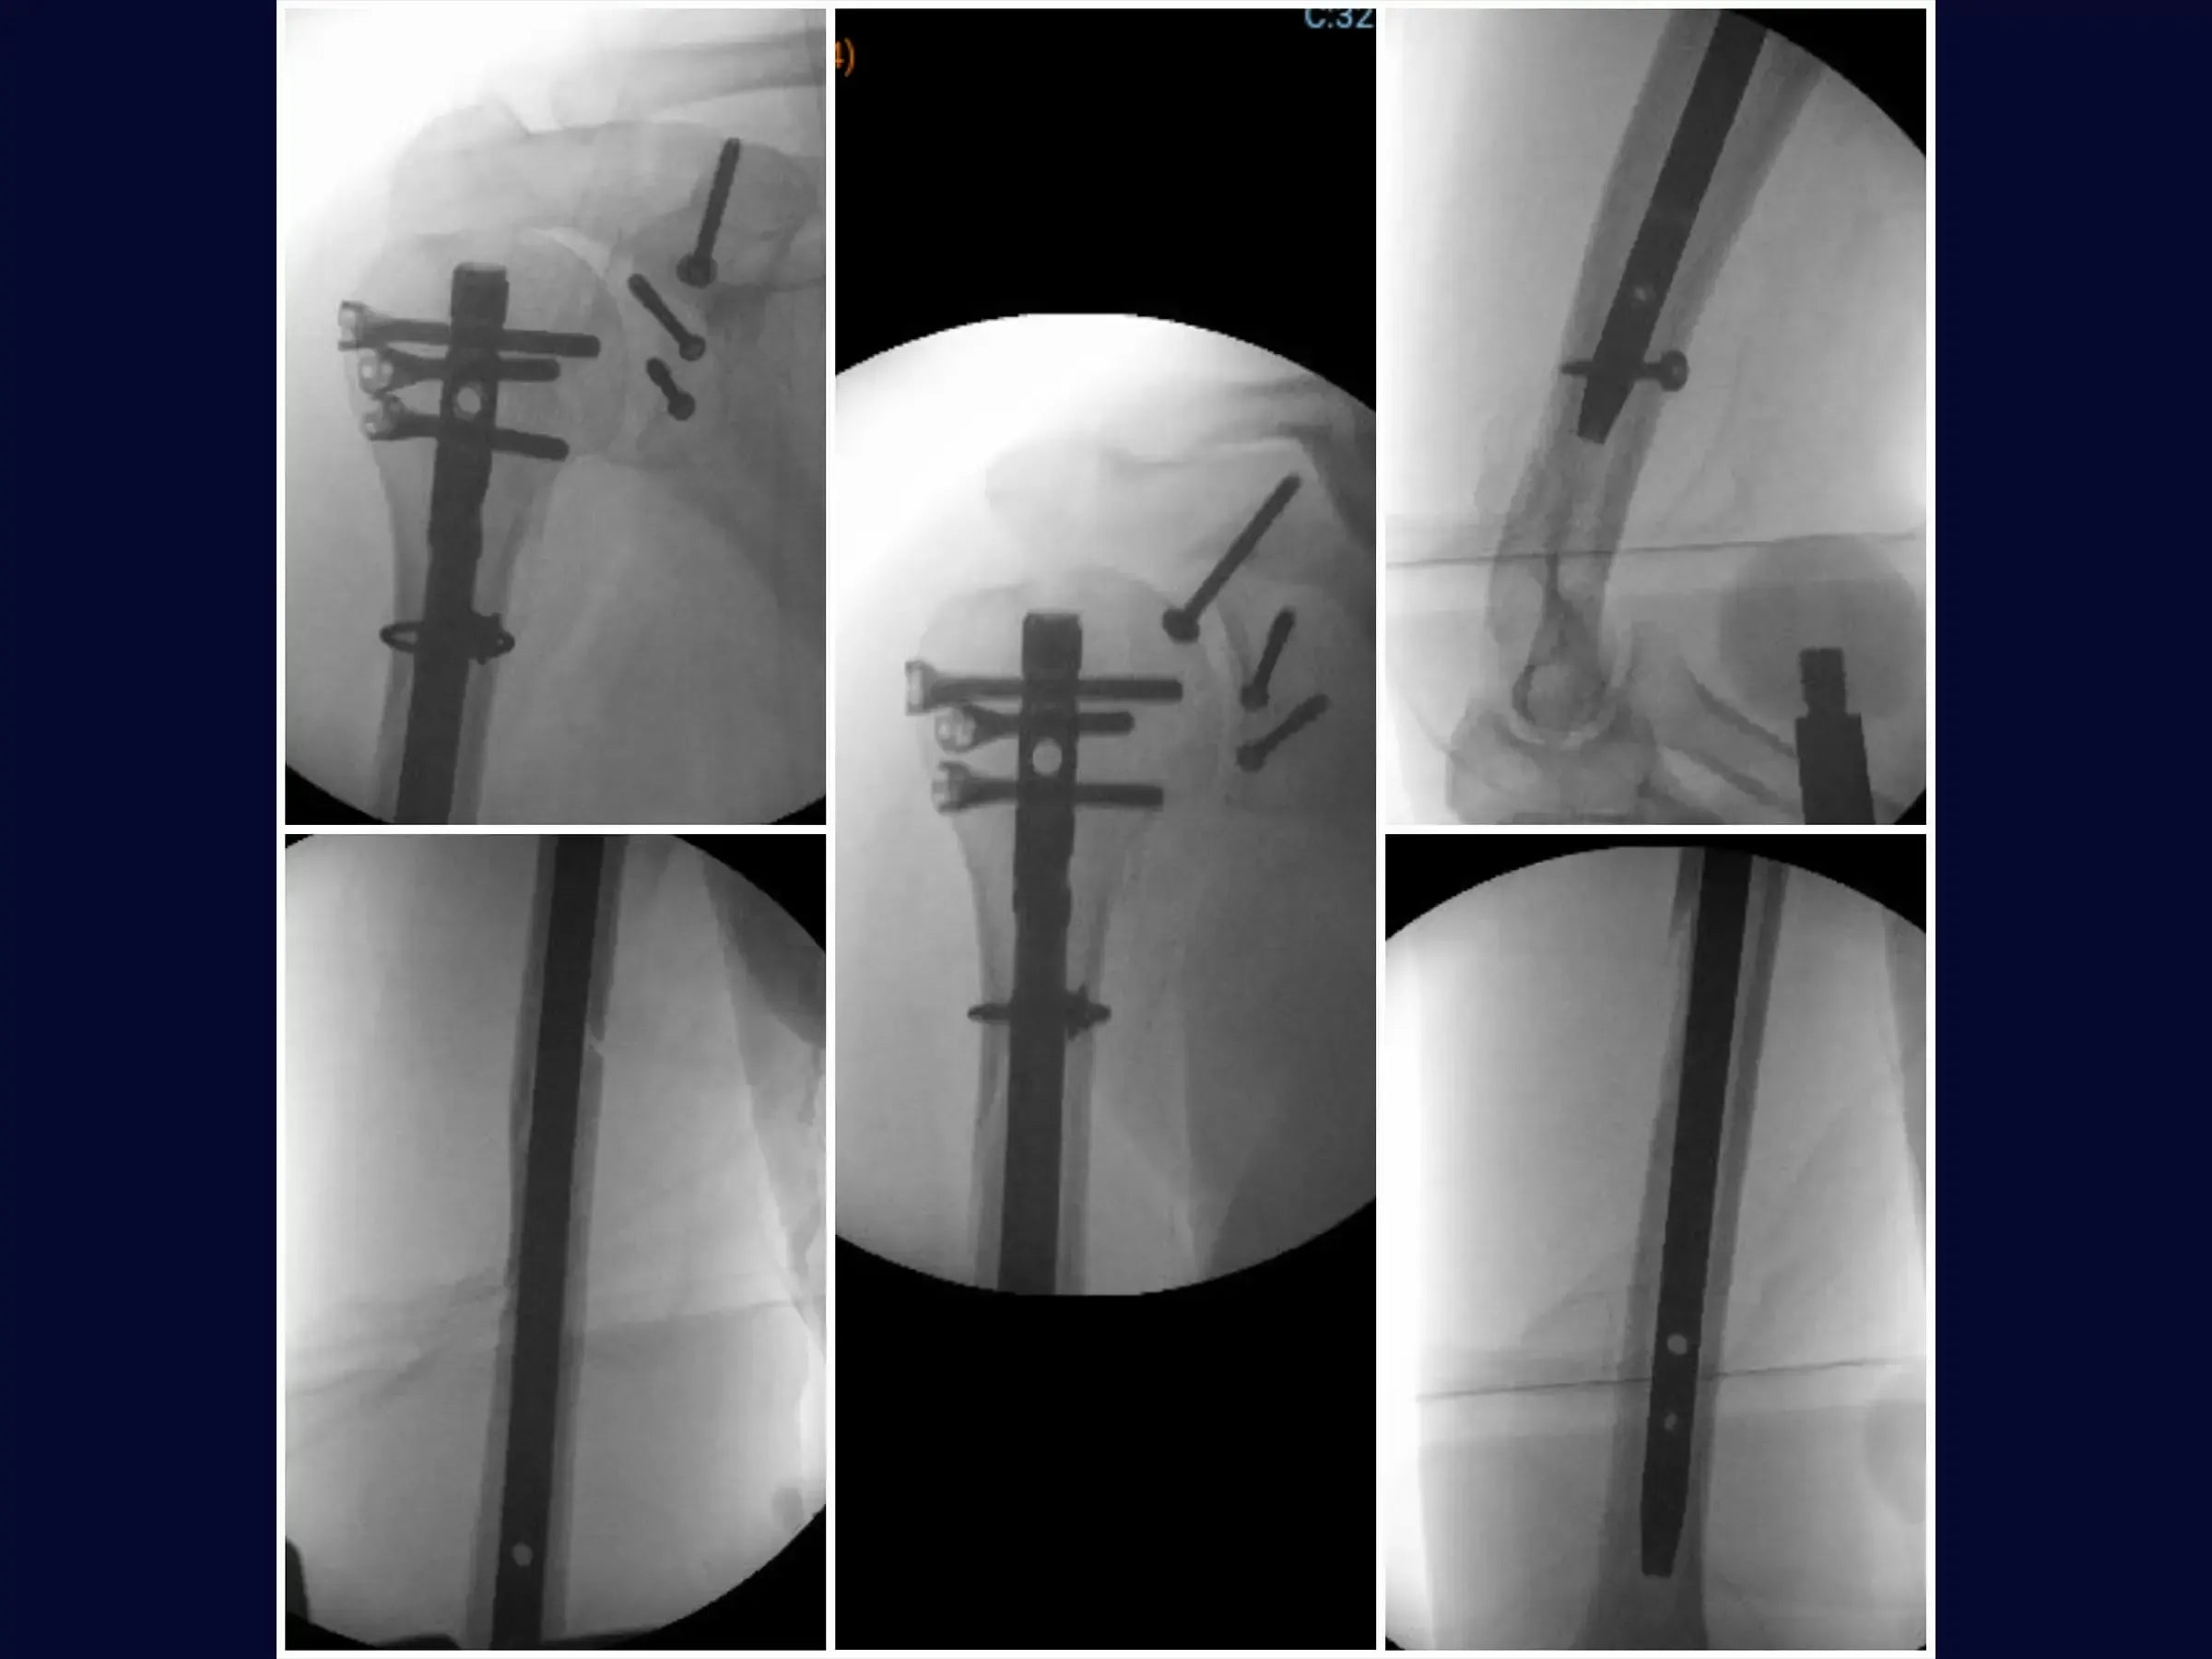

- Osteossíntese com haste intramedular e cerclagem no úmero.

- Fixação com parafusos na glenoide e coracoide.

- Reconstrução Segmentar do Úmero: Abordagem sistemática para identificação dos vértices da fratura, redução do segmento proximal e fixação com haste intramedular e parafusos proximais, complementada por cerclagem, para estabilidade e restauração anatômica.

- Fixação Precisa da Glenoide: Técnica de incisão e separação do subescapular da cápsula articular para exposição e redução do fragmento da glenoide, com inserção de fios guia e parafusos para assegurar a congruência articular e estabilidade.

- Estabilização do Coracoide: Demonstração da fixação do processo coracoide, preso ao tendão conjunto, com parafuso de compressão.